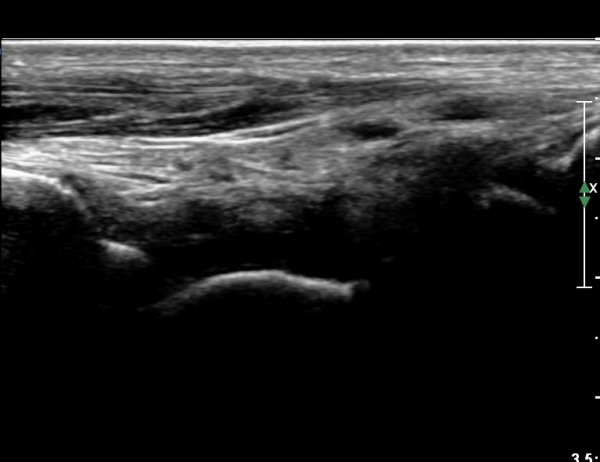

Àü°ÅºñÀδë Á¾´Ü¸é°Ë»ç¿¡¼­ Àü°ÅºñÀδëÀÇ ÆÄ¿­ÀÌ °üÂûµÈ´Ù(»çÁø 4, 5).

Àü°ÅºñÀδë Àü¹æ°ßÀΰ˻翡¼­ ÀÎ´ë ÆÄ¿­¿¡ ÀÇÇÑ °Å°ñÀÇ °úµµÇÑ ¿òÁ÷ÀÓÀÌ °üÂûµÈ´Ù(µ¿¿µ»ó Âü°í)